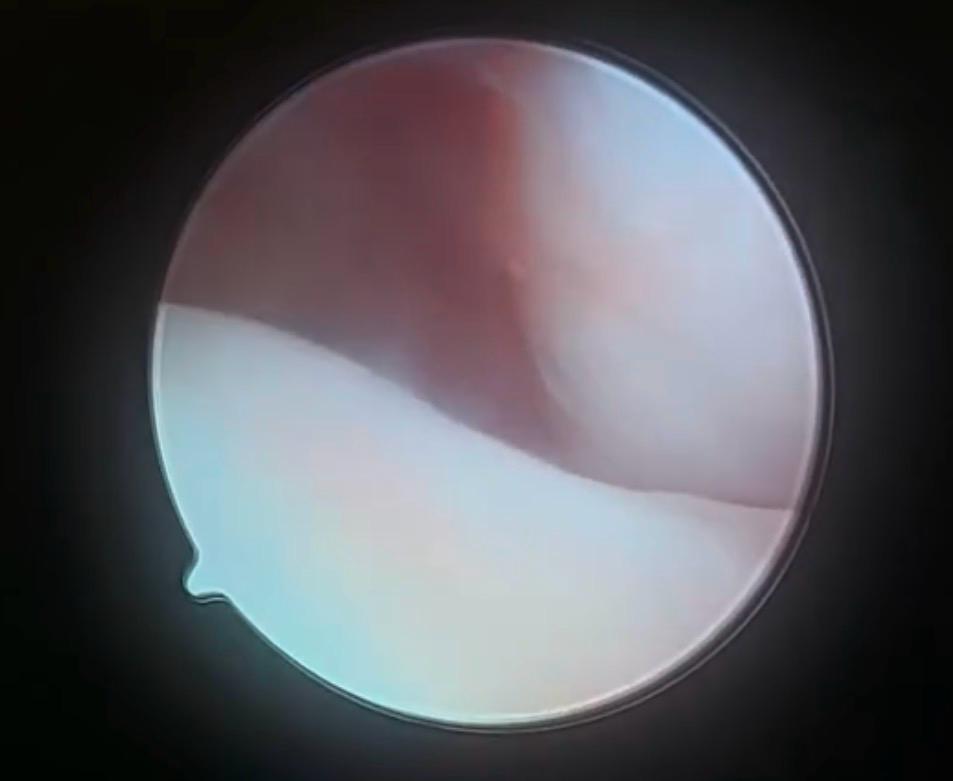

TEMPOROMANDIBULAR JOINT ARTHROSCOPY

Level I arthroscopy

This is a basic diagnostic and therapeutic procedure. It can be used to assess the degree of cartilage damage, inflammation and even disc perforation to accurately plan future management and treatment. We can irrigate the joint under pressure and even use injections to the joint. You will need to carry out some jaw movement exercises after the procedure.

Level II arthroscopy

This involves an additional small incision, using a technique called triangulation. The procedure takes a little longer, but it allows for the use of coblation to remove problematic or unhealthy tissues without damage to the surrounding area. A biopsy is also possible with this technique and medication can be delivered directly into the joint. The recovery time can be a little longer and it may be slightly more painful afterwards.

What does the procedure involve ?

During treatment, we insert the tiny 1.9mm arthroscope into your jaw joint while you are under general anaesthetic and your muscles are completely relaxed. A small cut is made in front of your ear for this, enabling us to use the camera to look for damage to your jaw joint.

Arthroscopy is combined with arthrocentesis but this is no longer a ‘blind procedure’ and the joint wash breaks down any loose material or inflammatory particles that may be damaging the joint.